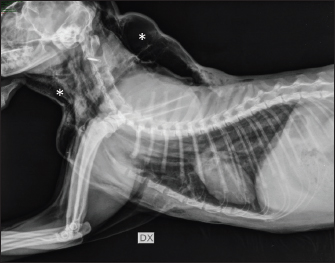

Fig. 1. Thoracic radiography (lateral view) performed upon patient arrival. Note the severe subcutaneous emphysema (white asterisk) in the head and neck region combined with moderate pneumomediastinum and mild pneumothorax.

On arrival, venous blood gas analysis revealed mild respiratory acidosis and mild hyperlactatemia (Table 1). The complete blood count revealed moderate thrombocytopenia and neutrophilic leukocytosis (Table 2). Biochemical analysis showed elevated liver and muscular enzyme levels and increased serum amyloid A levels (Table 2). Hypofibrinogenemia (1.36 g/l) with unremarkable coagulation time was evident. All abnormalities were consistent with the traumatic event suspected. Thoracic radiographs confirmed the presence of severe subcutaneous emphysema, associated with moderate pneumomediastinum and mild pneumothorax (Fig. 1). Computed tomography (CT) was scheduled for the following day due to the high suspicion of tracheal injury associated with cervical compressive myelopathy. The cat was hospitalized at the intensive care unit under strict monitoring, minimizing manipulation as much as possible. Fluid therapy was set at 2 ml/kg/h IV of lactated Ringer’s solution, together with analgesic therapy with methadone at 0.1 mg/kg IV every 4 hours, and antibiotic therapy with ampicillin-sulbactam 20 mg/kg IV every 8 hours. The cat was mildly symptomatic for the pneumothorax and was therefore managed conservatively. The following day, the clinical parameters were stable, and a progressive reduction of the subcutaneous emphysema and pneumothorax was noted; therefore, the patient was sedated with 0.2 mg/kg of methadone intravenously (IV) and 2 µg/kg of dexmedetomidine IV, and then placed in a VetMouseTrapTM to avoid intubation and general anesthesia. CT scans confirmed the moderate to severe subcutaneous emphysema, pneumomediastinum, and mild pneumothorax (Fig. 2). A dorsal parietal deformation of the cervical trachea of approximately 1 cm in length was observed, causing a mild reduction in the dorsoventral tracheal diameter. There were no other airway injuries. An incomplete fracture line of the caudal margin of the C4 vertebral arch was observed. The fracture line appeared slightly left-lateralized, with a caudal bone fragment approximately 2 mm long and 5 mm wide. This fragment was dislocated into the vertebral canal, narrowing the dorsoventral diameter, with subsequent compression of the spinal cord (Fig. 3). The CT scan confirmed the suspicion of C4 vertebral fracture and tracheal rupture. Endoscopic evaluation of the upper airways and surgical treatment with a dorsal approach for spinal decompression were scheduled for the following day.